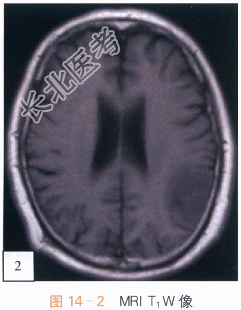

影像学资料:如图14-1~图14-4所示。

读片分析:头颅CT平扫,如图14-1所示,横断位示左颞叶见类圆形等高密度病灶,密度均匀、边界清楚,周围无明显水肿带,肿瘤临近蛛网膜下腔无增宽,脑沟脑回无受压或移位;头颅横断位MRI T₁W像,如图14-2,左颞叶类圆形低信号肿块影,内部信号稍欠均匀;邻近蛛网膜下腔无增宽,脑沟及脑回无明显受压移位;横断位T₂W像,如图14-3所示,肿块呈等高信号影,内部信号略不均匀,无明显囊变坏死及出血;增强扫描后横断位T₁W像,如图14-4所示,病灶强化稍欠均匀;病灶中必可见少许斑片状异常强化,余无明显异常强化,无脑膜尾征。